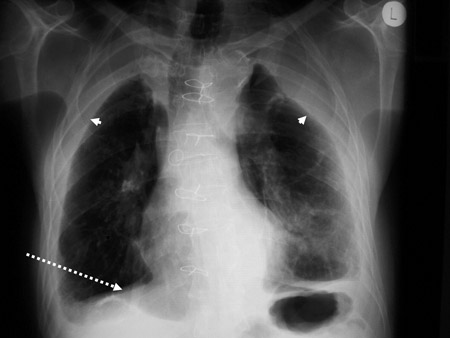

Diffuse pleural thickening (arrowheads) and elevated left hemidiaphragm (dotted arrow)

BMJ Case Reports 2009; doi:10.1136/bcr.06.2008.0253